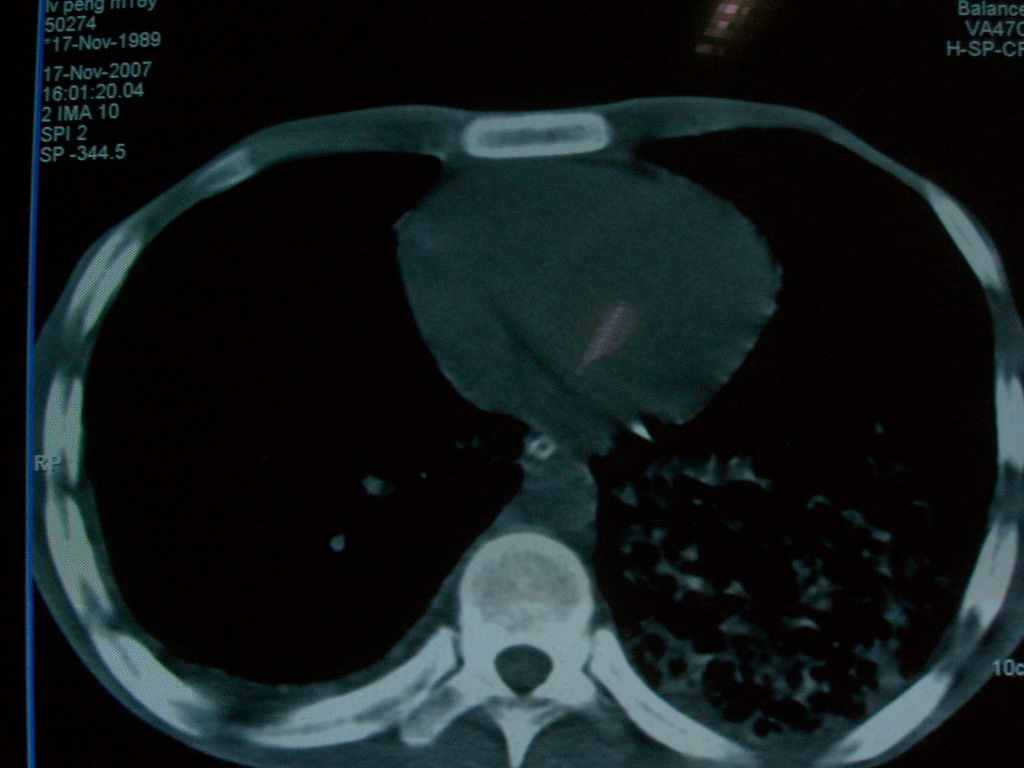

标题: CT10510:男.18岁,咳嗽咳痰两月.(有病理) [打印本页]

标题: CT10510:男.18岁,咳嗽咳痰两月.(有病理)

双肺布满大片状实变及网格状结节影,内参杂大小不等的气囊及空气支气管征,心脏增大。考虑:1 全身结缔组织疾病—系统性红斑狼仓?2 肺泡蛋白沉积症合并感染!

双肺布满大片状实变及网格状结节影,内参杂大小不等的气囊及空气支气管征,双侧胸膜腔少量积液,双下肺近膈面透亮度尚可,病人较年轻,病变较重(不知为什么上胃管?)考虑:1.胶原病肺部改变,2.组织细胞病x。结合实验室检查。

首先考虑组织细胞x病。两肺中上肺野多发囊腔,中下肺野内见多发小结节,并可见肺间质增厚。患者是男性,年龄较小。胶原性病变比较多见的类风湿、系统性红斑狼疮和硬皮病临床和影像均不是很支持,类风湿和系统性红斑狼疮的肺部表现最常见的是胸腔积液,硬皮病可见食管的扩张。

肺内多发斑片状、结节状、融合大片状及网格状影,多发薄壁空腔影,胸膜肥厚,纵隔、气管右移,考虑ⅲ型肺结核,多发空洞,继发肺间质纤维化。

双肺结核并播散.患者以肠梗阻入院,手术为肠结核.术后咳嗽做ct检查.